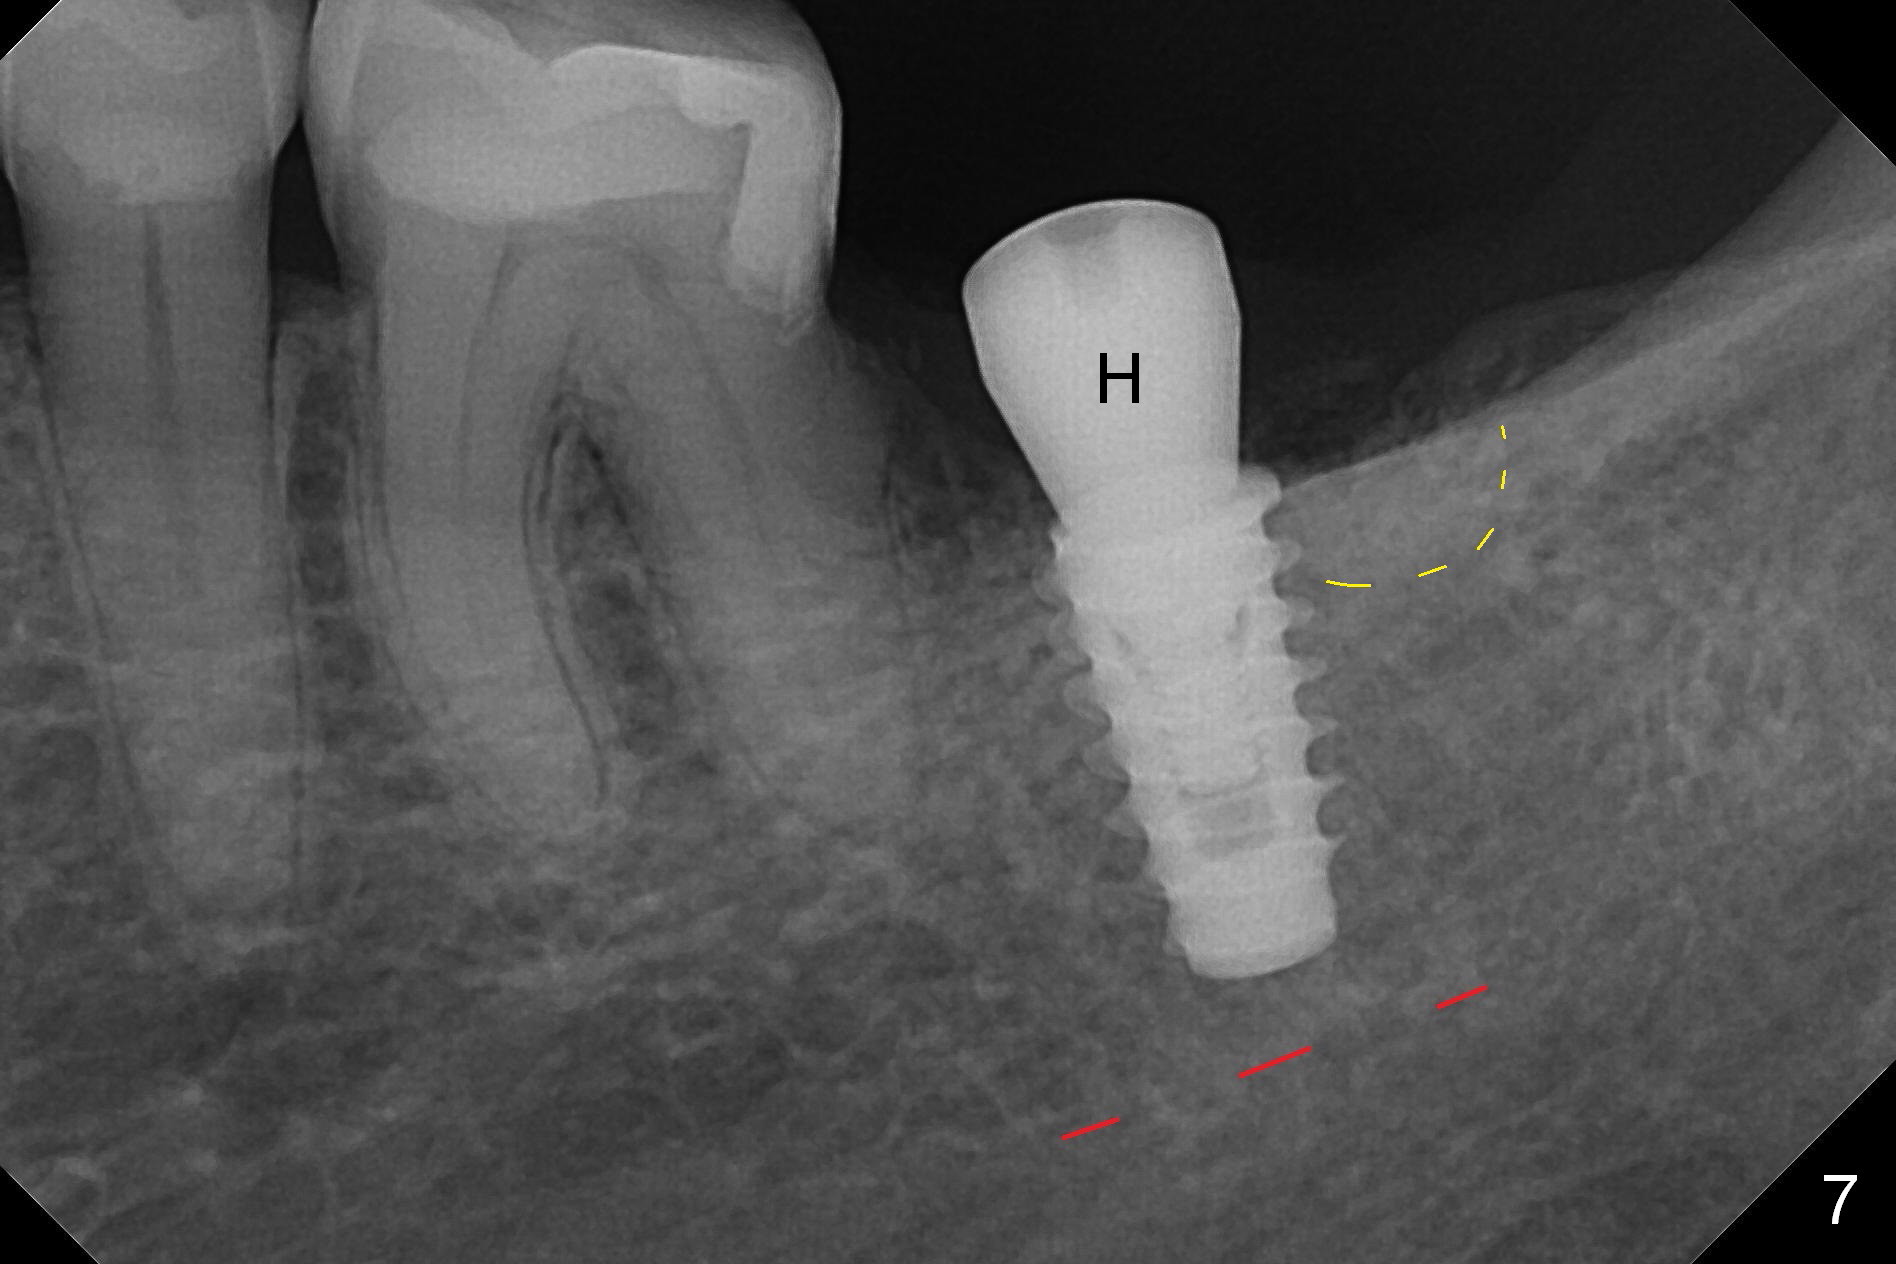

Preop palpation of the edentulous area at #18 does not show the flatness of the ridge top as shown by CBCT.  Incision reveals that the ridge is not as wide as CBCT indicates (Fig.1 (coronal section) between arrowheads).  In fact the ridge is concave (Fig.2 red dashed line).  Osteotomy is initiated in the middle of the concavity (Fig.2 green line) with insertion of 7 mm guide pin (Fig.3).   After removal of the pin, the osteotomy is moved buccally (Fig.4).  After Marking Bur and 4.3 mm Magic Drill, a 5x9 mm IBS implant is placed with 2.8 mm clearance from the Inferior Alveolar Canal (Fig.6).  Following deepening the osteotomy with Final Drill, the implant is placed deeper (Fig.7).  The osteotomy happens to be established in the mesial socket, since the distal socket has not completely healed (Fig.6 yellow dashed line).  Granulation tissue is removed.  Since the lingual crest is lower than the buccal one (Fig.1 B), there is lingual thread exposure after implant placement (Fig.5).  The exposed thread is covered by bone graft (autogenous bone, allograft and Osteogen, Fig.5 pink circles).  Some of the graft is apparently pushed into the distal socket (Fig.7 yellow dashed line) post GBR and suture.  As the implant is placed twice, insertion torque is <10 Ncm (although the implant is stable).  A 5x3 mm healing abutment is placed (Fig.7 H).